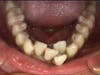

Crowded teeth can lead to tooth loss in adults.

Many adults suffer from crowded teeth in the front of both the lower and upper arches. This can lead to tooth loss. Invisalign can help.

Many adults think that if the lower front teeth are crowded and overlapping that they just have to live with it. Not true! Invisalign has become a great option for adults to be able to fix crowding before it leads to other issues such as tooth loss. When the arch becomes crowded, the teeth become harder to keep clean and the gums become inflamed and sometimes recession takes over because of this movement pushing a tooth out. A tooth can also become lodged behind other teeth creating discomfort.